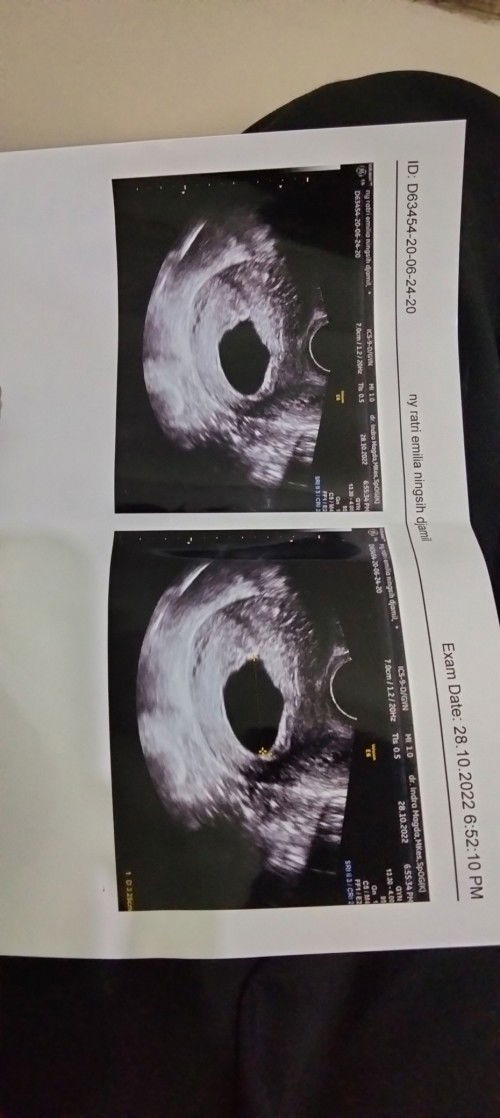

USG 9 Week Blighted Ovum (hamil kosong) ?!

Hai bunda2 siapa nih kmrin yg di vonis BO (hamil kosong), ada yg sudah USG lg ngga? share dong hasil terakhir USG nya apa setlh di vonis BO. aku Insha Allah minggu depan mau USG lg semoga sudah trlhat janin dan Djjnya... #seriusnanya #bantusharing #hamilkosong #infobayi #infobunda #SeputaranBunda #SeputarKehamilan

Hamil 8 minggu di vonis BO(hamil kosong) sama dokter

Bun ada yg pernh ngalamin hal yg sma ga' sih dg aku, tgl 15 kmrin aku usg uk 8w tpi dr. Bilang cma ada kntung nya sja janin tdak nampak. Jdi dr. Vonis aku BO dan nyaranin kuret di hari yg sma. Ukuran kantong kehamilan aku 3.27cm menurut hasil usg. Aku bertahan pertahanin khamilan aku krna aku rasa keluhan sprt kram perut bercak atau apapun it aku ga' rasain. Cuma yg aku rasain mual hilang dan nyeri pda paydra mulai brkurang. Menurut bunda2 aku harus bagaiamana, aku sngat amatir soal kehamilan soalnya ini khmilan pertama alu selama penantian 4 tahun. Mohon infonya bunda2🙏 #seriusnanya #hamilkosong #bantusharing